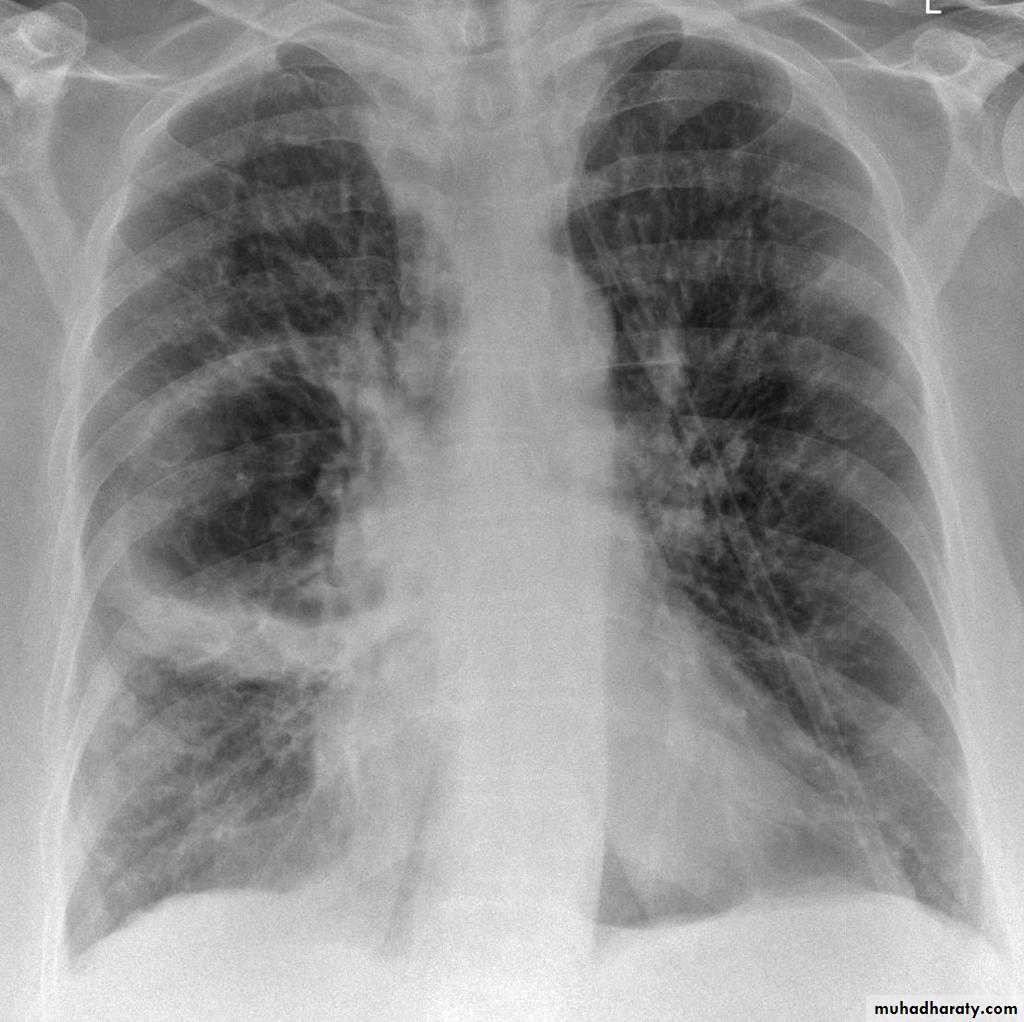

Bronchiectasis

59.Bronchiactasis